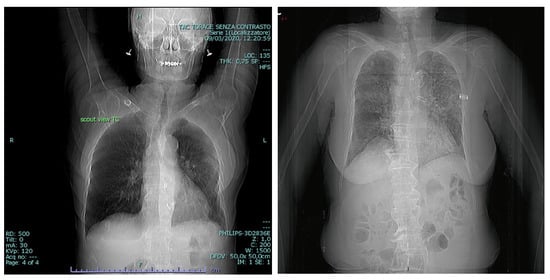

3.3. BIMCV COVID19+

3.4. RSNA